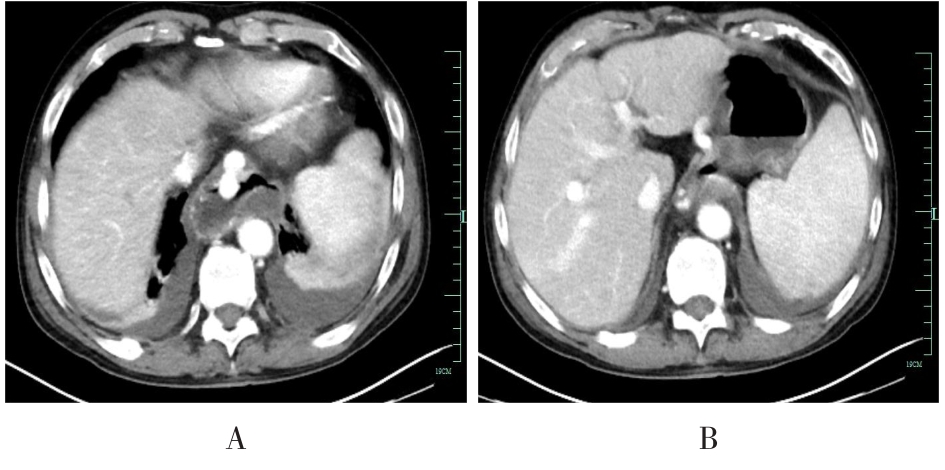

• 超声内镜引导下胃旁曲张静脉精准断流术治疗食管胃静脉曲张出血的疗效分析(附20例报告)

2025, 31(8):85-90. DOI: 10.12235/E20250036

摘要 (153) HTML (42) PDF 5.38 M (98) 评论 (0) 收藏

摘要:目的 探讨超声内镜引导下胃旁曲张静脉精准断流术治疗食管胃静脉曲张出血的疗效。方法 回顾性分析2024年1月1日-2024年12月31日于该院接受超声内镜引导下胃旁曲张静脉精准断流术治疗的20例肝硬化食管胃静脉曲张出血患者的临床资料,并评估治疗效果。结果 20例患者均顺利完成超声内镜引导下胃旁曲张静脉精准断流术;注射组织胶联合置入弹簧圈(16例)和单独注射组织胶(4例)均成功阻断胃旁来源的曲张静脉;所有患者均未发生穿孔、食管贲门狭窄、大出血、败血症和异位栓塞。1例单独注射组织胶的患者,术后胃旁曲张静脉少许渗血,经降低门静脉压力治疗3 d后好转,另1例单独注射组织胶患者,术后出现低热,抗感染3 d后体温恢复正常。结论 超声内镜引导下胃旁曲张静脉精准断流术治疗食管胃静脉曲张出血的临床疗效好,异位栓塞、大出血、感染和穿孔等并发症少,但仍需要密切随访,观察胃旁曲张静脉的排胶问题。